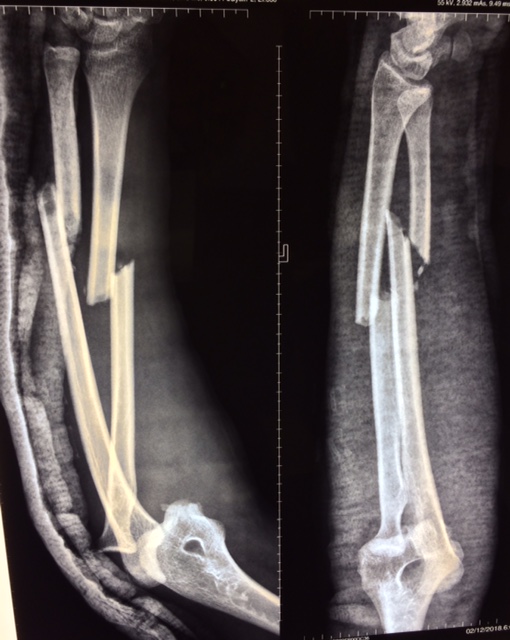

Парень, 24г., Авария, ЧМТ, перелом обеих костей предплечья, вывих локтевого сустава и перелом короноида (?).Рана 1 см, ушита при поступлении. Без осложнений, кисть - норм. функция.

Подскажите последовательность фиксации (исходя из Вашего личного опыта).

Мы склоняемся в пользу пластин сначала, затем устранения вывиха и возможно фиксации короноида. Нужно ли стабилизировать локтевой сустав и чем?